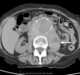

Retroperitoneal hemorrhage

Retroperitoneal bleeding is an accumulation of blood in the retroperitoneal space. Signs and symptoms may include abdominal or upper leg pain, hematuria, and shock. [Source: Wikipedia ]